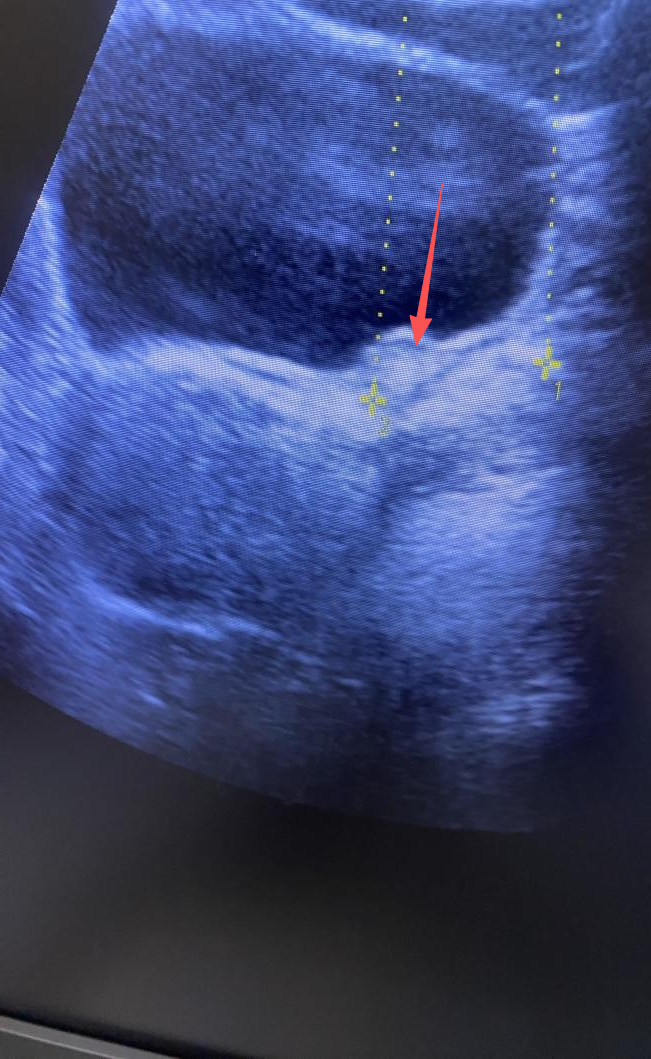

医师使用B超定位系统

给患者实施治疗

并在治疗床旁时刻监测碎石效果

图为输尿管末端结石

可见碎石中结石体积明显缩小